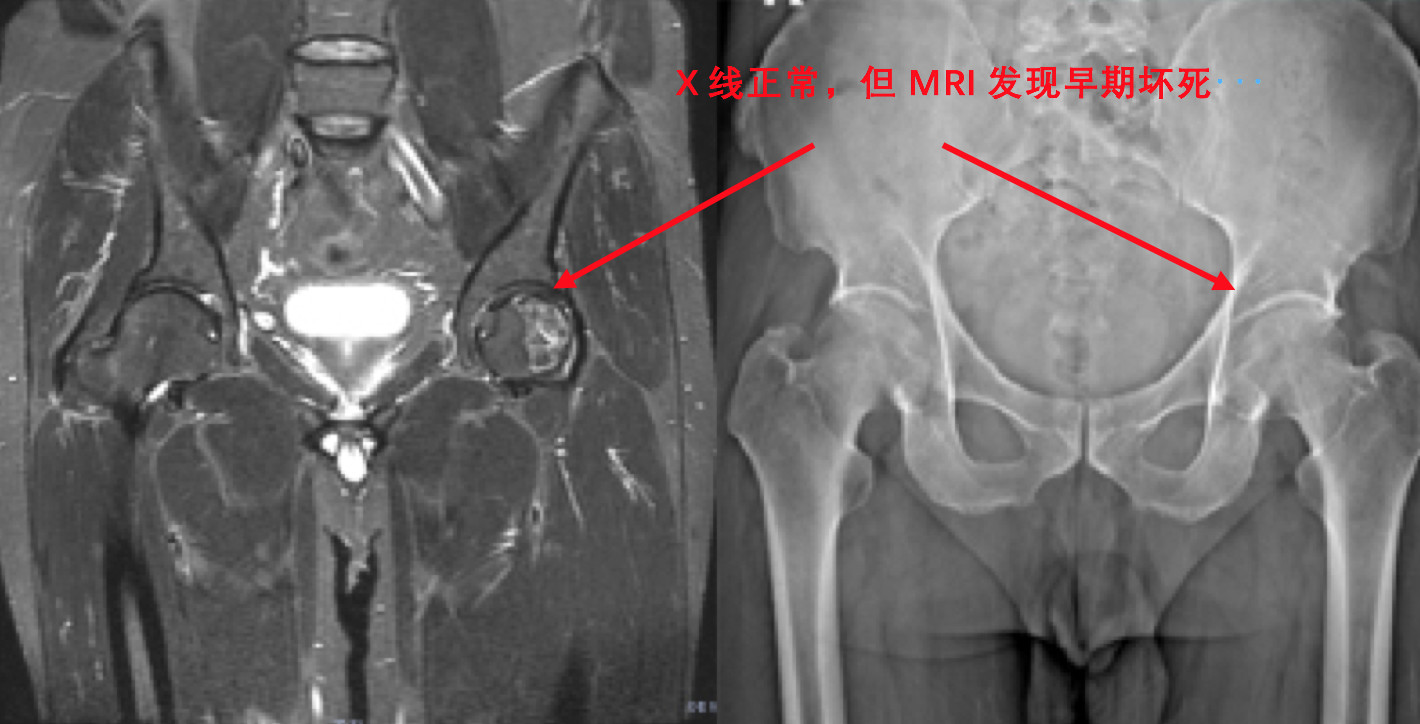

一般认为,股骨头坏死后6个月后,X线片才能出现异常。也就是说,X线发现股骨头坏死,提示股骨头至少在半年前已经发生坏死。早期诊断依靠MRI。有研究发现,在切断股骨头血供的数天后即可在MRI图像上发现异常。